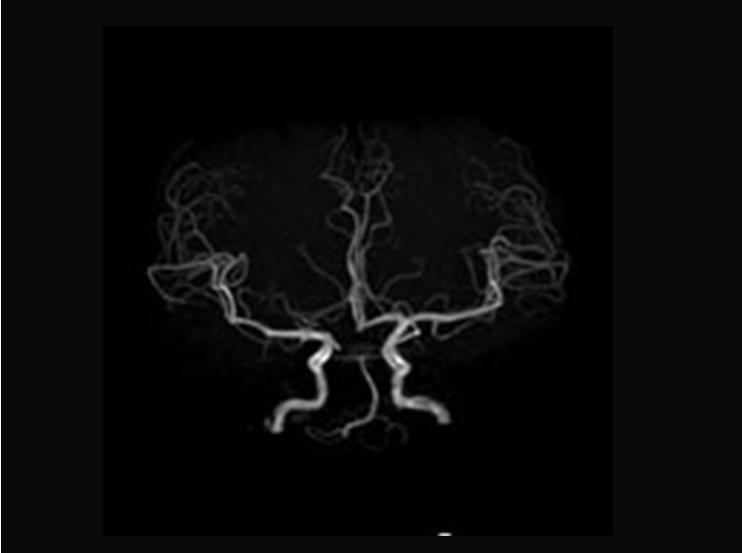

当院のX線CT装置は64列MDCT(マルチディテクターCT)と呼ばれ、ディテクター(検出器)が64列に配列され、広い範囲を短時間に撮影することが出来ます。通常の胸腹部の撮影に加え、血管を流れる造影剤を追いかけながら撮影を行う大動脈撮影や上下肢の血管撮影なども行えます。 また、心電図を同期させながら、造影剤を用いて高速で撮影することで、心臓が静止しているかのように撮影することができ、この撮影より冠動脈を画像化することができます。 X線CT装置で撮影した画像を用いて、下記の画像例のような心臓や血管の3D画像を作成することも私たちの仕事の一つとなっています。

※当院のX線CT装置で撮像した画像例です。

冠動脈3D

冠動脈MIP

脳血管画像